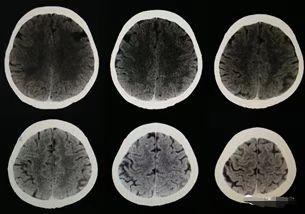

颅脑CTA:左侧颈内动脉海绵窦段混合斑块形成伴管腔轻度狭窄,右侧椎动脉V1段远段软斑块形成伴管腔轻中度狭窄。颈动脉CTA左侧颈内动脉颅内段少许钙化斑块形成。左侧椎动脉起源于主动脉弓(图3)。头颅SWI可见左侧颞顶叶出血性病变(图4)。

图3